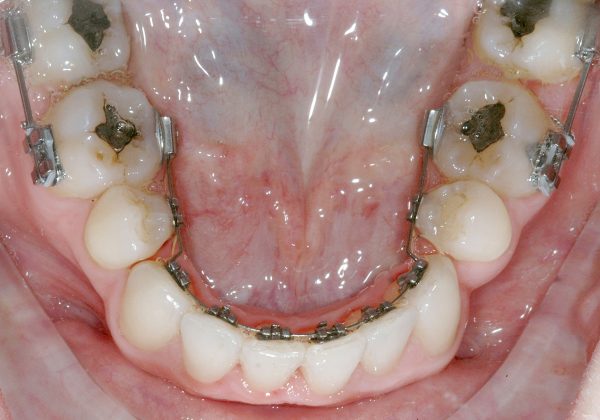

Una paziente di sesso femminile, 38 anni, già trattata ortodonticamente presso altra sede con apparecchiatura fissa a entrambe le arcate in età adolescenziale senza successiva applicazione di alcuna contenzione, si presenta alla nostra attenzione perché insoddisfatta dell’estetica del sorriso; richiede una valutazione per un trattamento ortodontico con apparecchiatura fissa linguale per la presenza di affollamento dentale a entrambe le arcate e difficoltà a mantenere una adeguata igiene orale; si riscontrano agenesia di entrambi gli incisivi laterali superiori (1.2 e 2.2) e del secondo premolare inferiore destro (4.5). Presentiamo la risoluzione del caso mediante trattamento ortodontico estrattivo a entrambe le arcate, eseguito con apparecchiatura linguale invisibile 2D e meccanica asimmetrica e seguito a medio termine da riabilitazione implanto-protesica e contenzione fissa.

Per formulare corretta diagnosi e piano di cura, lo studio del caso ha previsto la raccolta di documentazione completa standard, ovvero fotografie del viso e intraorali (Figure 1a-e), radiografia panoramica e teleradiografia del cranio in proiezione laterale (Figure 2a-b) per la relativa analisi cefalometrica e modelli di studio.

La valutazione clinica e gli esami effettuati confermano la presenza di agenesia degli incisivi laterali superiori (1.2 e 2.2) e del secondo premolare inferiore destro (4.5).

L’analisi ortodontica e la valutazione parodontale, con particolare riferimento alla posizione della radice del canino superiore destro (1.3), distoinclinata e trasposta alla radice del primo premolare (1.4) come evidente dalla radiografia panoramica e dalle immagini intraorali, ci hanno guidati nella programmazione di un trattamento estrattivo asimmetrico a entrambe le arcate.

Il protocollo terapeutico ha previsto l’estrazione del primo premolare inferiore sinistro (3.4) e del primo superiore destro (1.4), l’applicazione di una apparecchiatura fissa linguale 2D e di una meccanica asimmetrica di ancoraggio e movimento ortodontico a entrambe le arcate (Figure 3a-b).